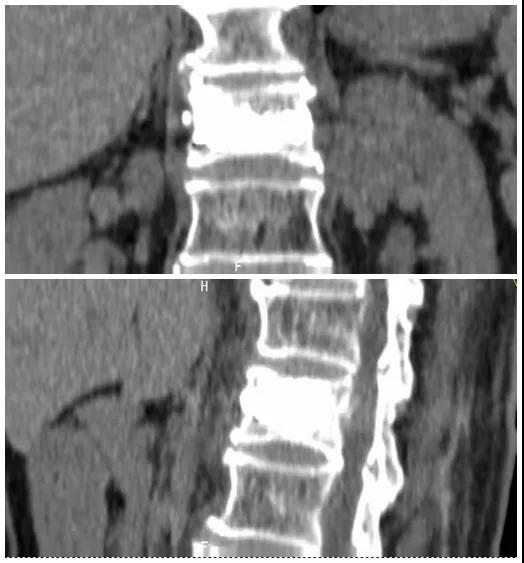

術(shù)后復(fù)查CT可見(jiàn)骨水泥彌散充分

經(jīng)術(shù)前分析詳細(xì)評(píng)估,由骨科副主任張宏宇及科室團(tuán)隊(duì)順利為患者進(jìn)行了經(jīng)皮穿刺椎體成形術(shù),術(shù)后患者疼痛明顯減輕。同時(shí),科室團(tuán)隊(duì)還為她制定了科學(xué)的抗骨質(zhì)疏松治療,目前患者已康復(fù)出院。